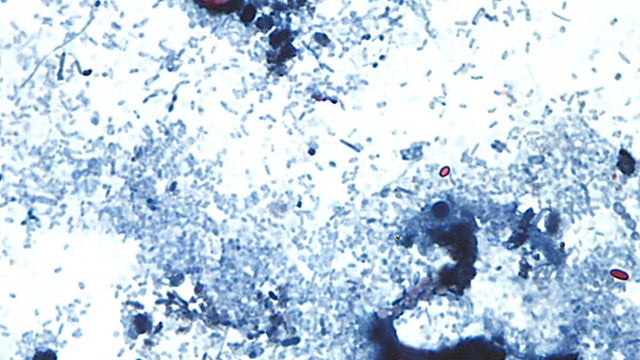

Michigan is experiencing its largest outbreak of a parasitic infection, called cyclosporiasis, that causes severe diarrhea.